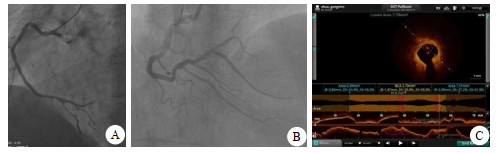

1 资料与方法病例1,男,63岁。持续性胸背部不适伴胸闷气促6 h于2021年12月5日急诊以AMI入院,心电图提示下壁Q波形成(图 1)。肌钙蛋白(cardiac troponin, cTnI)7.10 ng/mL,肌酸激酶同工酶(creatine kinase isoenzyme, CK-MB)22.5 ng/mL(图 2)。急诊经皮冠状动脉介入治疗(percutaneous coronary intervention, PCI):右冠脉左室后支(posterior branches of left ventricular, PL)100%(图 3A),为罪犯血管,右冠脉后降支(posterior descending artery, PDA)75%狭窄(图 3B),左前降支(left anterior descending artery, LAD)80%狭窄。开通罪犯血管PL,球囊扩张后置入2.5 mm×31.0 mm支架,患者胸闷气短症状缓解。考虑到罪犯血管放支架后血流动力学尚稳定,非罪犯血管是否缺血,是否需要干预治疗,决定行非罪犯血管FFR测定。测定结果PDA 0.76,LAD 0.69均需干预治疗,行OCT检查观察狭窄处冠脉钙化及纤维化的严重程度来决定是急诊干预还是择期干预。检查结果示PDA冠脉内轻度纤维化,决定急诊干预,置入2.5 mm×31.0 mm支架,再行FFR测定为0.88(阴性),而LAD的FFR为0.69(阳性),OCT检查冠脉内严重环状钙化伴重度纤维化并脂质斑块形成(图 3C),而且病变较长,急诊干预有引起冠脉夹层弊病的可能,为安全改为择期处理。

| A为PL 100%;B为开通PL、PDA后FFR 0.76,支架植入后FFR 0.88;C为LAD,OCT冠脉内严重环状钙化 图 3 病例1的冠脉造影及OCT检查结果 |